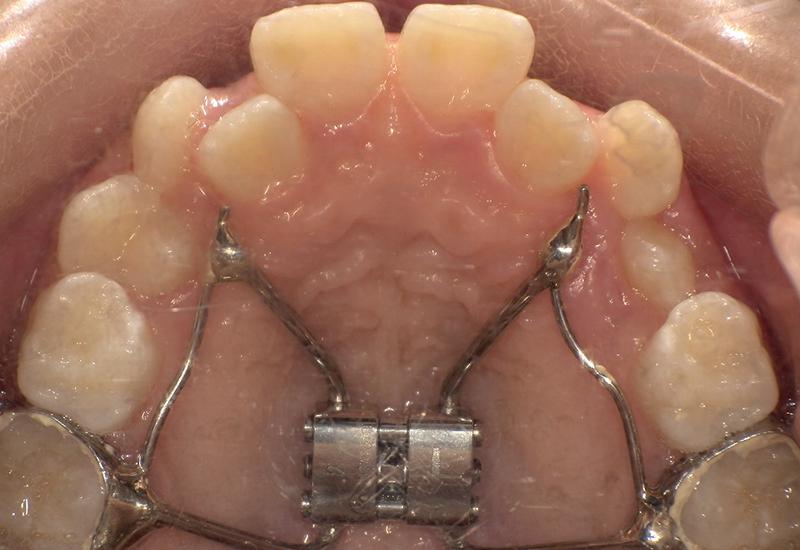

症例② シェイプメモリーアライナーによる混合歯列期の矯正

治療期間 6ヶ月

治療時の年齢/性別 10歳 / 女性

かかった治療費 440,000円

治療方法 シェイプメモリーアライナー

注意点・リスク 今、現在萌えてきている永久歯を動かす為、なるべく早く治療を終了させる